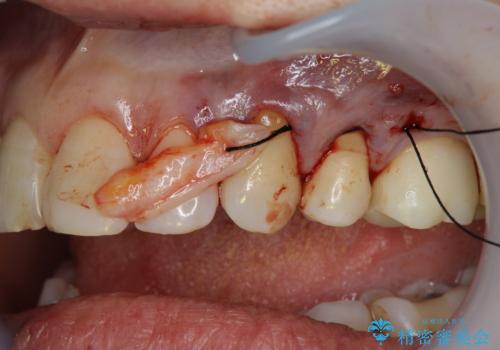

改善を図るため、結合組織移植を行い歯ぐきの再生を計画します。

手術を行い歯ぐきの位置が改善することで歯がしみる症状が大幅に改善されたと満足いただくことができました。

手術に合わせて歯ブラシの練習を行うことで再発を未然に防ぐことができます。